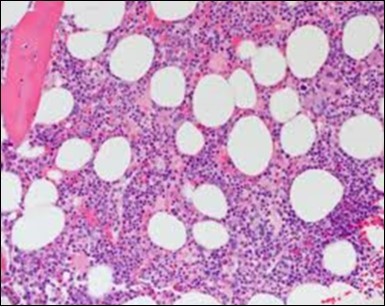

The classic hairy cell is medium sized with a magnitude of 10-14µm. The moderately abundant or variable cytoplasm may be transparent or mildly basophilic. The cellular surface with the characteristic serrated perimeter depicts innumerable fragile or stout extensions of cytoplasm ,particularly discernible on the phase contrast and electron microscopy. The cytoplasm may exhibit vacuoles with occasional azurophilic granules4. The nucleus may be elliptical or reniform, folded or indented with a coarse, reticulated or a finely dispersed chromatin and inconspicuous nucleoli along with infrequent mitosis. Bone marrow aspiration or bone marrow trephine biopsy may be inadequate for diagnosis in 30%-50% individuals4. The trephine sections of the bone marrow may depict a characteristic interstitial pattern of leukaemic infiltration. Generally the bone marrow is hyper-cellular, though it may be hypo-cellular in 10-15% individuals4. The leukaemia cell ingress may be diffuse or partial, although diffuse infiltration is frequent. The partial variety of leukaemic dissemination may be ineptly categorized with an indeterminate differentiation from the uninvolved marrow. The malignant insertions may initially emerge as miniature, undefined, cellular loci. The formalin fixed, paraffin embedded sections may elucidate a crystalline zone or a “halo” appearance of the cells with a circumscribed nucleus on account of the plentiful cytoplasm4. The cellular margins may be intertwined. Fixation of bone marrow smears with Zenker’s fixative may demonstrate a retracted cytoplasm of the hairy cells with a consequent disconnected structure. The bone marrow in the absence of a malignant process may be hypo-cellular or hyper-cellular. Reticulin stains may delineate an enhanced accrual of broad, dense reticulum fibres surrounding the aggregates of leukaemia cells with the fibrous circumlocution of individual malignant cell and fibrotic extensions into the abutting, uninvolved bone marrow4.

The leukaemia cells may enunciate a characteristic immune phenotype, crucial for a confirmatory diagnosis. The peripheral blood mononuclear B cell population may display a kappa or lambda light chain restriction. The phenotype of classic hairy cell leukaemia may be delineated by concurrent, immune reactive CD19+ CD20+,CD 11c+, CD25+, CD103+ and CD123+. An intensely immune reactive CD200+ and a non reactive CD27- antigen may be present2, 4. Evaluation of a trephine bone marrow biopsy and bone marrow aspirate may define the degree of tumour infiltration. A dry tap on account of prominent bone marrow fibrosis may be elucidated at preliminary diagnosis. A decline in the normal haematopoiesis may account for a hypo-cellular marrow in 10% instances. Gradation of cellular infiltrating of the leukaemia within the bone marrow may be appropriately investigated with immune –histochemical stains2, 4. Immune staining for CD20+, annexin 1 and VE1 (a BRAF V600E stain] may validate the diagnosis and precisely analyse the extent of malignant bone marrow infiltration[8]. Determination of BRAF V600E mutation may be critical in therapeutically non responsive individuals with applicable standard therapy or in instances of multitudinous reoccurrences[9]. Deploying inhibitors of BRAF V600E gene may be efficacious in patients impervious to approved therapy. The mutation necessitates a comprehensive scrutiny of the implicated individuals with a sensitive molecular assay which may discern up to < 10% of the hairy leukaemia cells appearing in the peripheral blood smears or bone marrow aspirates diluted with peripheral blood or aspirates elucidating a dry tap[2,4]. Allele specific polymerase chain reaction (PCR) or a next generation sequencing may be optimally employed to circumvent false negative outcomes. If the leukaemia cells are sparse or if particularly sensitive & efficacious molecular techniques are not accessible, the application of appropriate immune histochemical stains to the bone marrow biopsy such as a BRAF V600E mutation stain (VE1) may detect the hairy cells and conclusively diagnose the condition[2,4,10]. Figure 1, Figure 2, Figure 3, Figure 4, Figure 5, Figure 6, Figure 7, Figure 8, Figure 9, Figure 10, Figure 11, Figure 12, Figure 13, Figure 14.

Figure 8.HCL: widely disseminated hairy cells within the bone marrow trabaculae(24).

Figure 9.HCL: hairy cells within a bone marrow trephine biopsy(25).